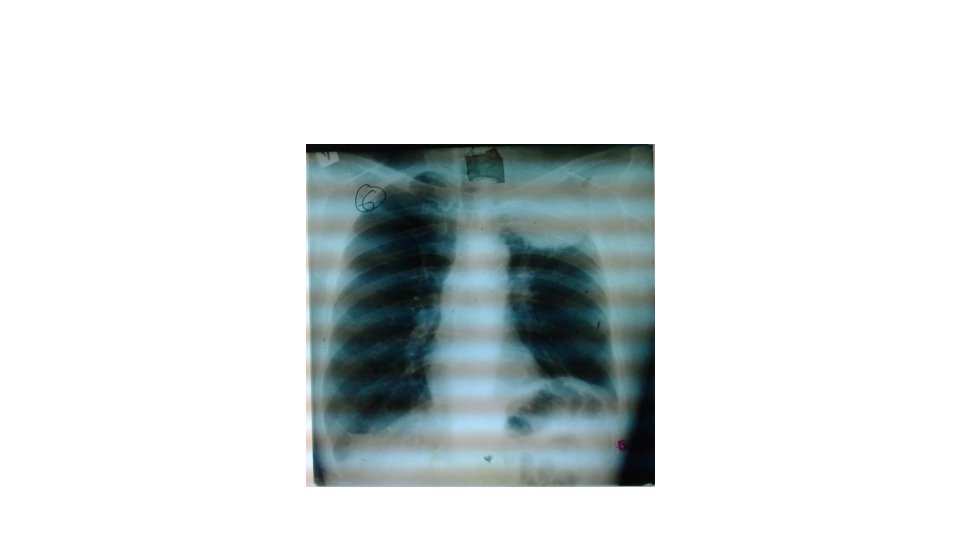

Tuberculose • La caverne c’est une clarté La région X de l’hémi thorax X set le siège d’une image cavitaire grossièrement arrondie mesurant environ ……cm ou ovalaire à grand axe (vertical, horizontal, oblique)à paroi épaisse à limite interne nette régulière et à limite externe flou Il faut préciser: unique ou multiple, associée ou non à un infiltrat, se continue avec la région hilaire par une bande claire réalisant l’image dite en raquette